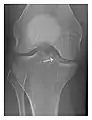

Figure 1: A 56-year-old woman presenting with left knee pain after a fall. (a) Initial anteroposterior radiograph was considered normal, however, subtle cortical disruption of the anterior rim of the medial tibial plateau, medial to the tibial spine, is noted (arrow). (b) Coronal T1-weighted MRI confirms the cortical disruption (arrow) and shows extensive fracture through the proximal tibia. (c) Coronal proton density-weighted image with fat saturation shows extensive edema in the subchondral bone. Note also hypersignal adjacent to the medial collateral ligament corresponding to a grade I sprain (arrowheads).[1]

- a

- b

- c